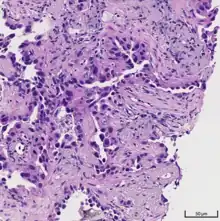

Histopathology

If possible, a biopsy of any suspected lung tumor is performed in order to make a microscopic evaluation of the cells involved and is ultimately required to confirm diagnosis.[7] Biopsy should be attempted in distant lesions first to establish a histologic diagnosis and to simultaneously confirm metastatic staging. The biopsy material is also used to analyze whether the tumor express any specific mutations suitable for tageted therapy (e.g. EGFR mutation or ALK mutation). Biopsy can be accomplished via bronchoscopy, transthoracic needle biopsy, and video-assisted thorascopic surgery (VATS).[4]

Adenocarcinoma of the lung tends to stain mucin positive as it is derived from the mucus-producing glands of the lungs. Similar to other adenocarcinoma, if this tumor is well differentiated (low grade) it will resemble the normal glandular structure. Poorly differentiated adenocarcinoma will not resemble the normal glands (high grade) and will be detected by seeing that they stain positive for mucin (which the glands produce). Adenocarcinoma can also be distinguished by staining for TTF-1, a cell marker for adenocarcinoma.[29]

As discussed previously, the category of adenocarcinoma includes are range of subtypes, and any one tumor tends to be heterogeneous in composition. Several major subtypes are currently recognized by the World Health Organization (WHO)[1] and the International Association for the Study of Lung Cancer (IASLC) / American Thoracic Society (ATS) / European Respiratory Society (ERS):[30][31][32] lepidic predominant adenocarcinoma, acinar predominant adenocarcinoma, papillary predominant adenocarcinoma, micropapillary predominant adenocarcinoma, solid predominant adenocarcinoma, and solid predominant with mucin production. In as many as 80% of these tumors, components of more than one subtype will be recognized. Surgically resected tumors should be classified by comprehensive histological subtyping, describing patterns of involvement in increments of 5%. The predominant histologic subtype is then used to classify the tumor overall.[2] The predominant subtype is prognostic for survival after complete resection.[33]

To reveal the adenocarcinomatous lineage of the solid variant, demonstration of intracellular mucin production may be performed. Foci of squamous metaplasia and dysplasia may be present in the epithelium proximal to adenocarcinomas, but these are not the precursor lesions for this tumor. Rather, the precursor of peripheral adenocarcinomas has been termed atypical adenomatous hyperplasia (AAH).[10] Microscopically, AAH is a well-demarcated focus of epithelial proliferation, containing cuboidal to low-columnar cells resembling club cells or type II pneumocytes.[10] These demonstrate various degrees of cytologic atypia, including hyperchromasia, pleomorphism, prominent nucleoli.[10] However, the atypia is not to the extent as seen in frank adenocarcinomas.[10] Lesions of AAH are monoclonal, and they share many of the molecular aberrations (like KRAS mutations) that are associated with adenocarcinomas.[10]